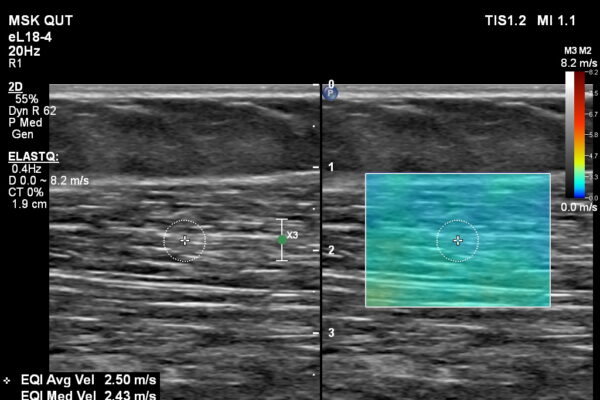

Shear Wave Elastography of Soft Tissues

Shear Wave Elastography (SWE) is an advanced ultrasound technology that can assess the biomechanical properties of tissue by measuring the velocity of shear waves travelling through the medium. At QUIQ…